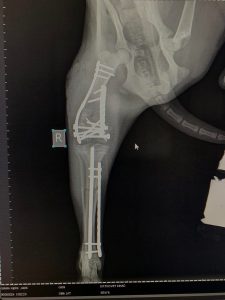

- Liječenje prijeloma kostiju, uključujući intraartikularne frakture

- Hirurške intervencije na zglobovima(artrotomija, artrodeza)

- Korektivne osteotomije za ispravljanje deformiteta